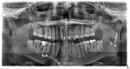

Полгода назад получил травму — двойной перелом нижней челюсти со смещением. Поставили две пластины, удалили осколок кости примерно 3 см, зуб в области перелома не удалили.

В данный момент наблюдается потемнение десны в месте перелома и выделение гноя. В моем городе нет ЧЛХ. Стоматологические клиники отвечают неоднозначно. Одни говорят, что необходимо просто удалить зуб, другие отвечают, что необходима операция (повторное шинирование, удаление зуба и чистка, с возможной переустановкой пластины).

Зуб из линии перелома необходимо удалить, т.к. он служит источником инфекции, отсюда и рецидив. Также провести ревизию воспалительного очага.